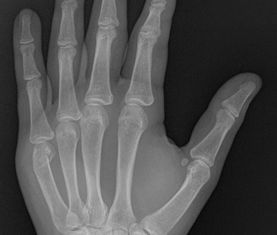

Imaging

X-ray is mandatory in clinically suspected fractures to confirm the diagnosis and define the fracture morphology to help decide on treatment. Occasionally CT scans are required in the case of complex fractures.